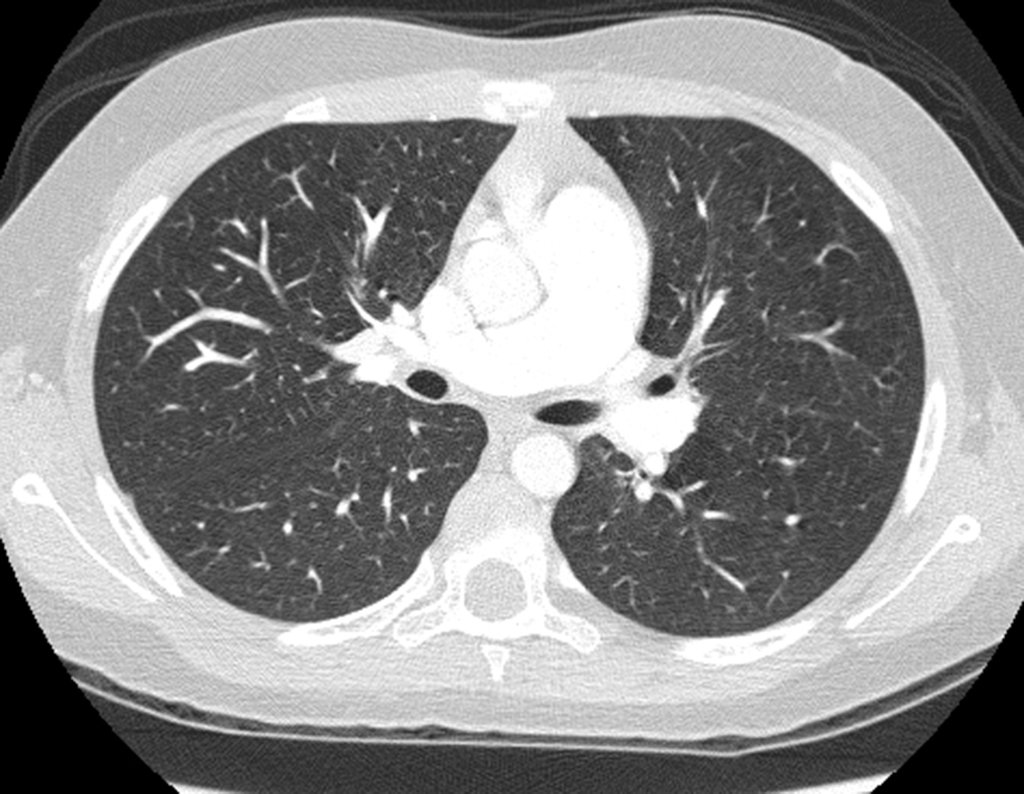

Después de una semana, el 14/08/2015, se retiró la férula y se encontró edema residual en la muñeca y dolor local. La semana siguiente, el 17/08/2015, fue evaluado por otro ortopedista quien repitió las radiografías y diagnosticó un quiste en el radio y una pequeña fractura arriba, figuras 1 a 5.

El domingo 20/09/2015, después de un día de mucha actividad física, caminar, nadar, se presentó aumento de edema y dolor en la muñeca derecha. Al día siguiente se realizaron nuevas radiografías de muñeca, que identificaron la evolución de la lesión, figuras 6 y 7.